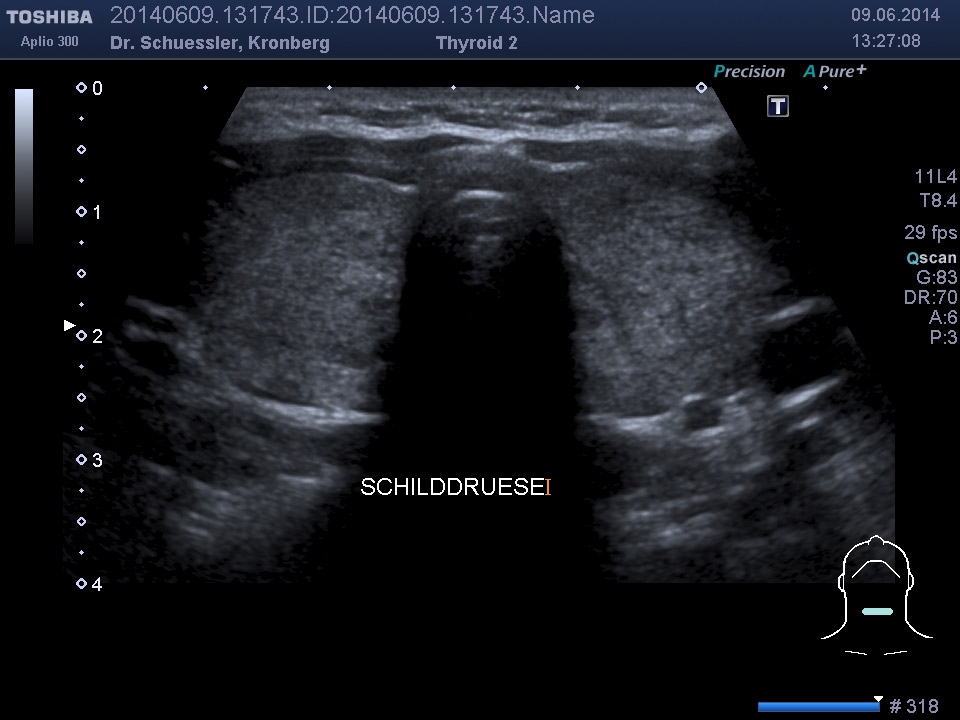

Farbkodierte Ultraschalluntersuchung der Schilddrüse

Die Ultraschalluntersuchung der Schilddrüse ist das Standardverfahren zur Beurteilung der Schilddrüse. Sie ist einfach durchzuführen und für den Patienten nicht belastend.

Mit dieser Untersuchung lassen sich die Schilddrüsengröße, ihre Struktur und auch Knoten, Zysten oder entzündliche Veränderungen sichtbar machen. Durch Hinzunahme der Farbkodierung lässt sich auch die Durchblutungssituation der Schilddrüse sichtbar machen.

Ultraschalluntersuchung am liegenden Patienten.